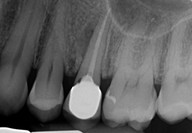

Galleria fotografica